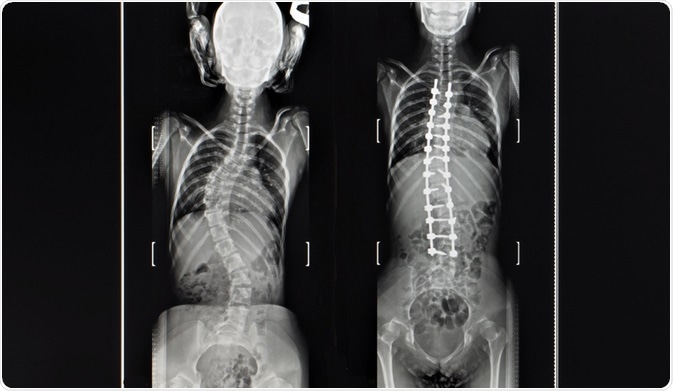

For teenagers or young adults, a spinal fusion may be needed in the treatment of scoliosis. This involves the straightening of the spine using metal rods and bone grafts to secure the spine in the correct positioning. This is considered to be a major operation and the rods typically remain in the patient's spine permanently as long as no problems arise.